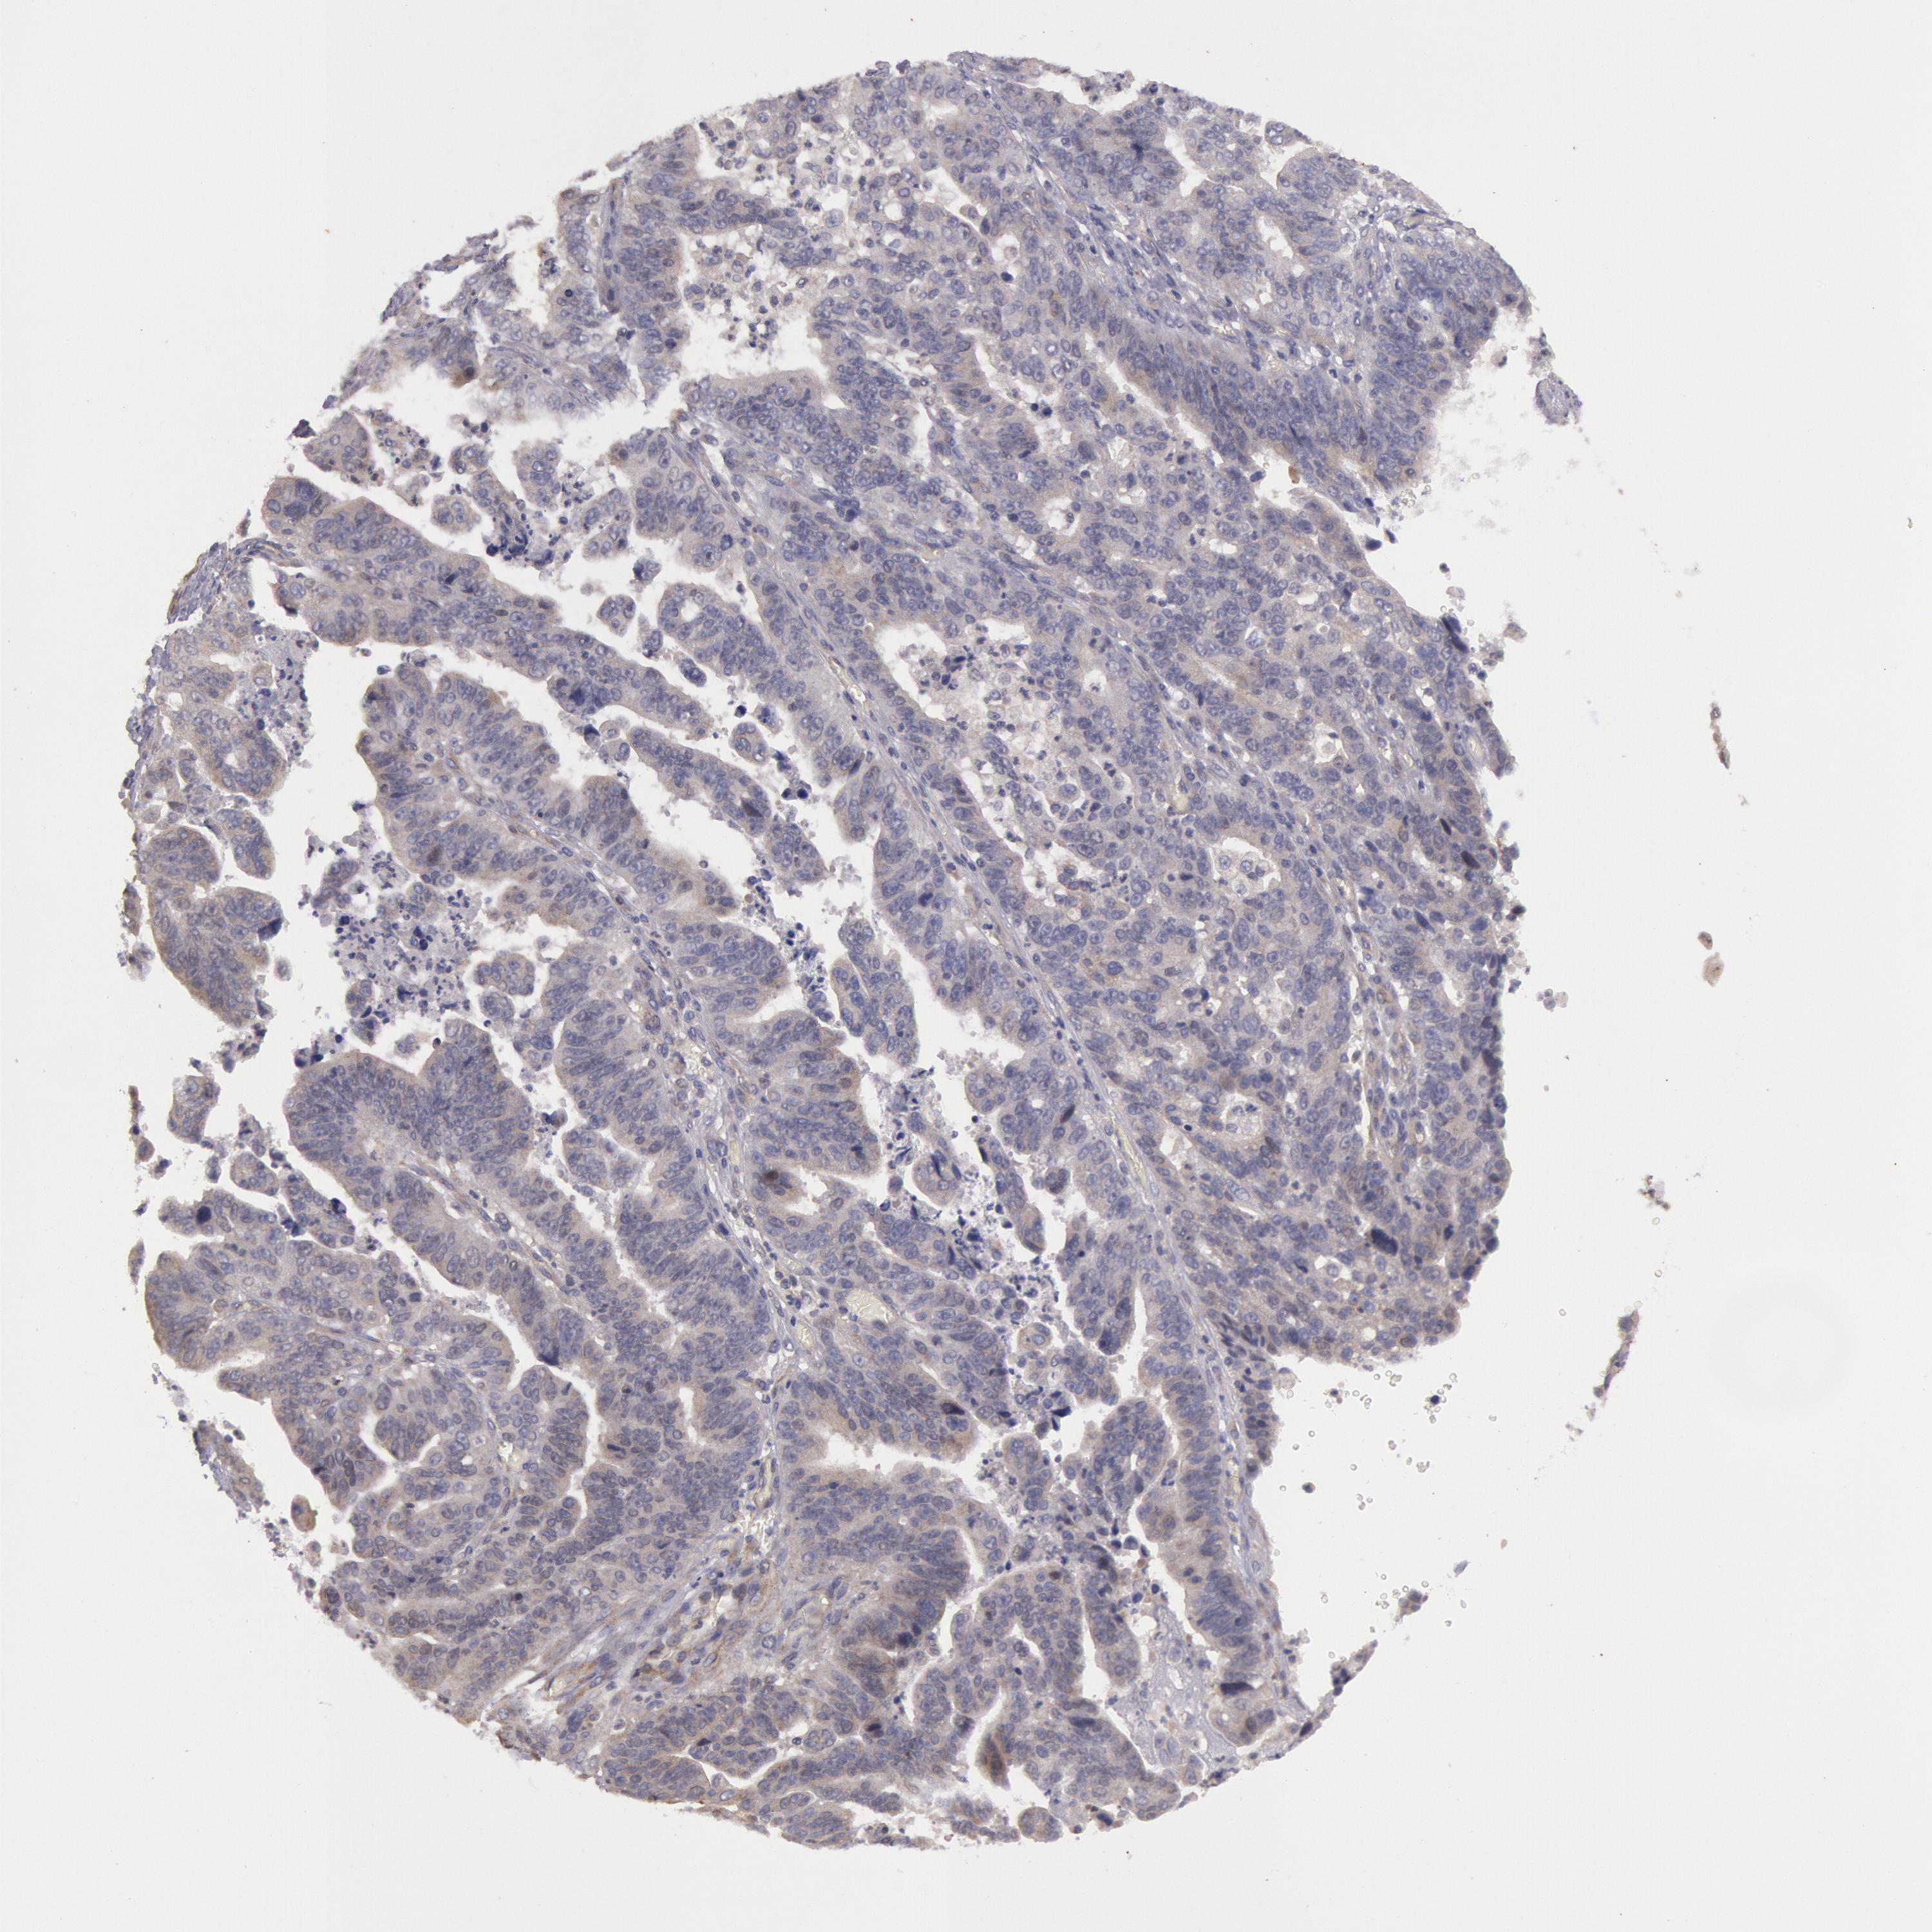

STOMACH CANCER - Protein expressioni

A mouse-over function shows sample information and annotation data. Click on an image to view it in a full screen mode. Samples can be filtered based on level of antibody staining by selecting one or several of the following categories: high, medium, low and not detected. The assay and annotation is described here.

Note that samples used for immunohistochemistry by the Human Protein Atlas do not correspond to samples in the TCGA dataset.

Antibody stainingi

Antibody staining in the annotated cell types in the current human tissue is reported as not detected, low, medium, or high, based on conventional immunohistochemistry profiling in selected tissues. This score is based on the combination of the staining intensity and fraction of stained cells.

Each image is clickable and will lead to virtual microscopy that enables deeper exploration of all samples and also displays staining intensity scores, fraction scores and subcellular localization as well as patient and tissue information for each sample.

Antibody HPA001196

Staining

High

Medium

Low

Not detected

Intensity

Strong

Moderate

Weak

Negative

Quantity

>75%

75%-25%

<25%

None

Location

Nuclear

Cytoplasmic/membranous

Cytoplasmic/membranous,nuclear

Adenocarcinoma, NOS